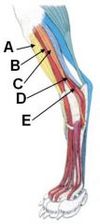

A - Cranial tibial m.

B - Long digital extensor m.

C - Peroneus longus m.

E - Lateral digital extensor m.

D - Peroneus brevis m.